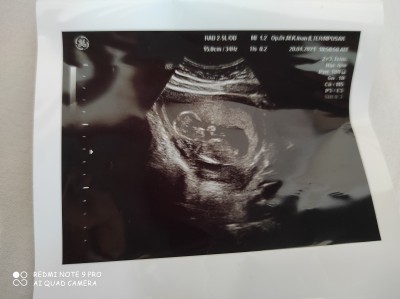

Cinsiyet tahmini yapabilir misiniz hanımlar 13+3 oldum :)

Çıkıntı var sanki canım hayırlısı olsun

Pipi yani çıkıntı dediğim

Direk erkek diyesim geldi canm

Erkek gbiii sanki :)

Maşallah erkek oldugu cok belli canm hayirlı olsun :)

pipisi apaçık ortada canm ondan anladım :))

Erkek gibi sanki ama tam da bilemedim